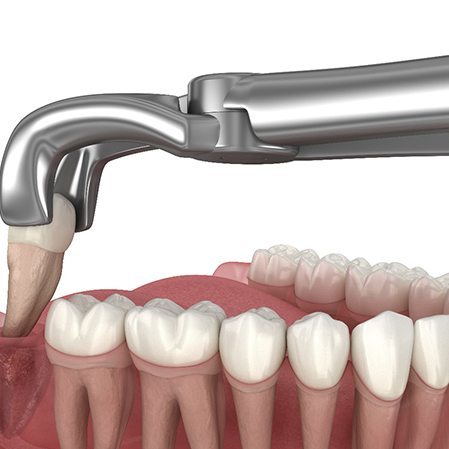

There are two ways to remove wisdom teeth: simply or surgically. If the molar has partially erupted and is slightly visible above the gumline, your dentist in San Antonio can use a dental elevator and dental forceps to lift the tooth from its socket and gently move it back and forth until it detaches.